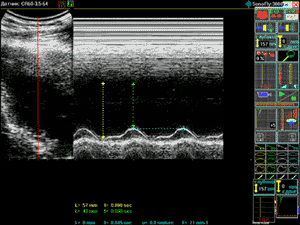

Особую ценность при кардиологическом исследовании представляет режим М - сканирования. Такое сканирование происходит по одному, узконаправленному ультразвуковому лучу. Аппарат для ультразвуковой диагностики ( УЗИ ) SonoFly-3000 позволяет выполнять кардиологические исследования в режимах В, В+В, В+М и М.

Аппарат для ультразвуковой диагностики (УЗИ) SonoFly-3000 позволяет получить качественное изображение сердца, его четырех камер, клапанов в движении в реальном масштабе времени. Удобство и функциональность режимов M и B+M, вычисление основных сердечных индексов - дополнительные аргументы при выборе SonoFly-3000 в качестве рабочего места врача-кардиолога.